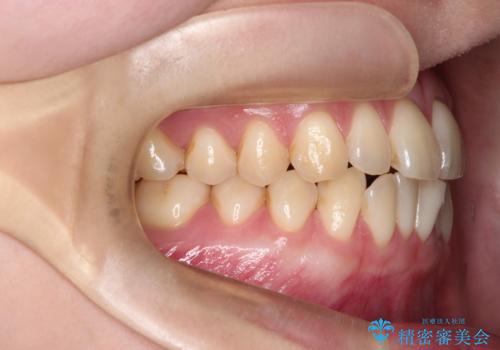

- 「下の前歯が斜めになっている」を主訴に来院された患者様です。

下顎前歯に叢生があり、右上2は反対咬合の状態でした。

下顎前歯の叢生がとれ右上2の反対咬合も改善し患者様にも満足していただけました。治療期間は1年~1年半を見込んでいましたが、患者様の協力もあり10か月で矯正を終えることが出来ました。